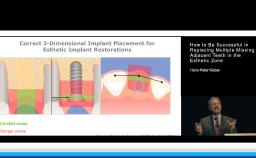

This presentation introduces and addresses the physiologic changes that occur in the oral cavity with age. Particular focus is given to the dental and periodontal tissues, oral mucosa, salivary glands, and the alveolar process (or alveolar bone). A differentiation is made between changes associated with age and those associated with pathology or therapy, particularly in regard to bone. General considerations are provided regarding treatment planning of elderly patients for dental implants.

- discuss the influence these changes may have on planning for implant placement and restoration